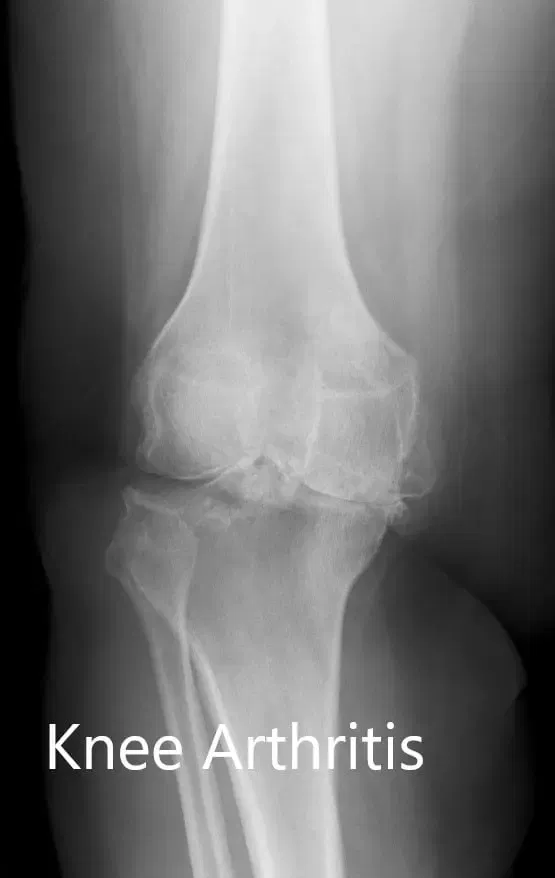

Imaging studies revealed severe tricompartmental osteoarthritis of the right knee. Considering the patient’s lifestyle limiting knee pain, he was advised customized total knee replacement. Risks, benefits, and alternatives were discussed with the patient. He agreed to go ahead with the surgery.

Preoperative X-ray of the right knee showing AP and lateral views.